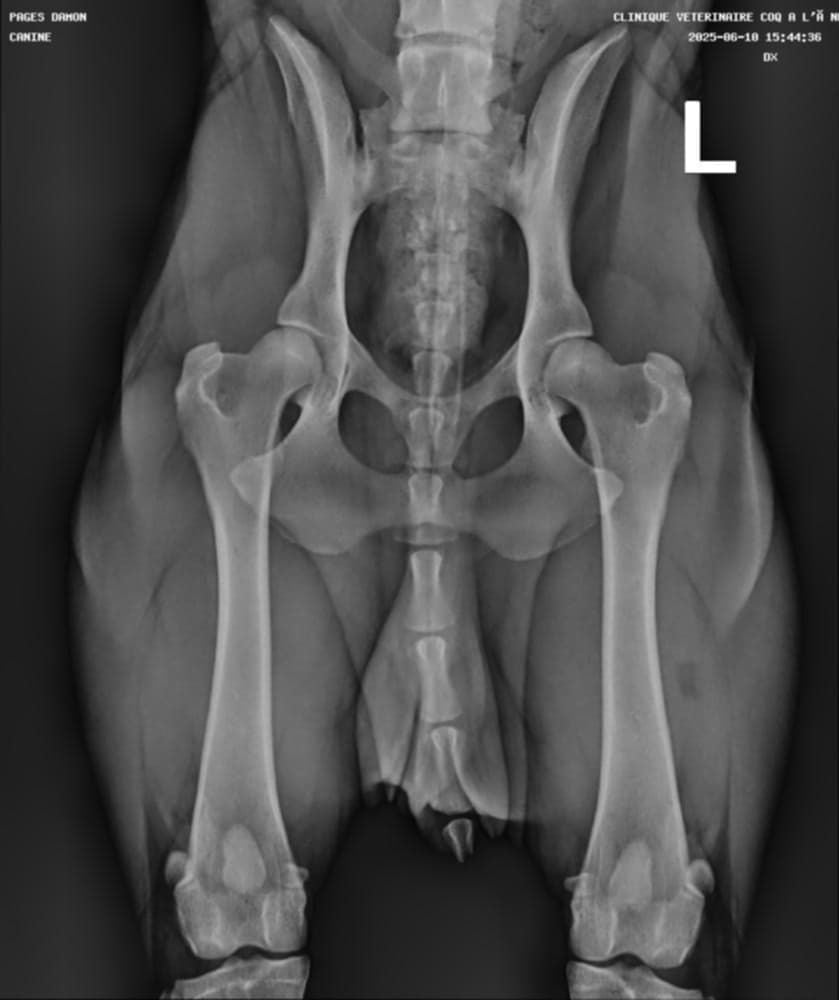

Radio officielle hanches